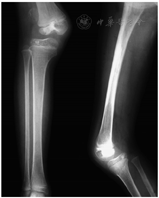

术后4个月,因胫骨内翻畸形行近端骨骺外侧阻滞术,6个月后获得矫正(图4)。术后10个月,因下肢内旋和股骨超长2 cm,行股骨下端外旋短缩截骨术,3个月后截骨愈合。

术后19年复查,下肢发育基本对称,膝关节伸屈0°-140°,无不适症状,能参加体育活动。X线片示胫骨平台平整对称,股胫角170°,髌股关节正常,骨硬化无进展(图5)。Kujala髌股关节功能评分98分,Tegner评级4级。生育一女,发育正常。